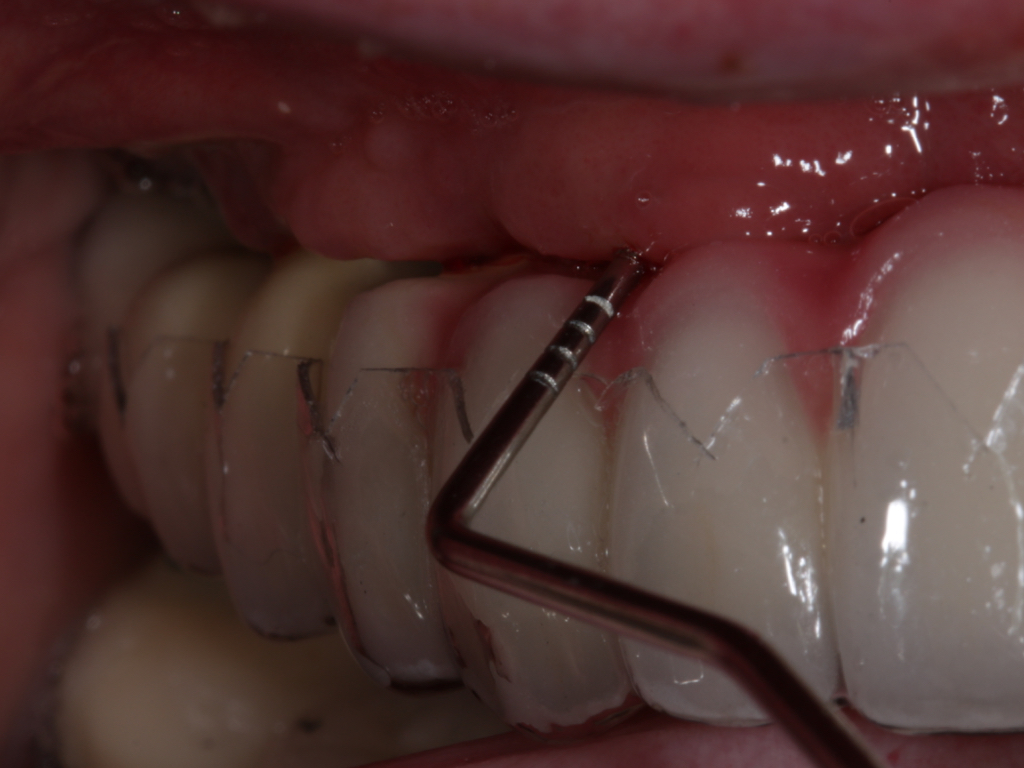

Clinical PPD is measured to the nearest millimeter by means of a graduated periodontal probe with a standardized tip diameter of approximately 0.4 mm to 0.5 mm. Several factors can influence the measurements made with periodontal probes, including: the thickness of the probe used5; the angulation and positioning of the probe depending on anatomic features, such as the contour of the tooth surface (Figure 1 through Figure 3)6; the graduation scale of the probe5; the pressure applied on the instrument during probing6; and the degree of inflammatory cell infiltration in the soft tissue and accompanying loss of collagen.7

Fig 1. Inaccurate probing angle wrongly indicates probing depth at 3 mm, which does not correspond to the radiographic finding shown in Fig 2.

Figure 1

Fig 3. Correct angulation of the probe demonstrates 6-mm probing depth.

Figure 3